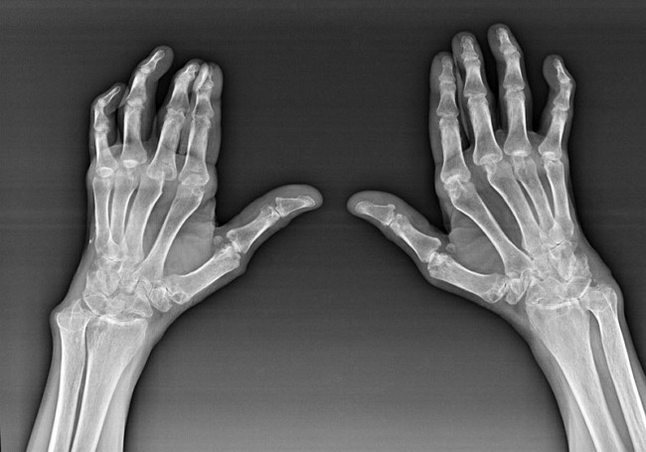

Polyarthrite rhumatoïde

La polyarthrite rhumatoïde est une maladie dans laquelle le système immunitaire humain endommage les propres tissus du corps. En d'autres termes, la polyarthrite rhumatoïde est une auto-immunpathologie. Cette maladie est également systémique car de nombreux tissus sont affectés ((((Muscles, articulations, vaisseaux, etc.) et les organes (Cœur, reins, poumons, etc.) dans le corps.

Malgré le fait que la polyarthrite rhumatoïde est une maladie systémique, les articulations souffrent davantage, tandis que la lésion d'autres tissus et organes est en arrière-plan. Avec cette maladie, presque tous les types d'articulations de pinceau peuvent être affectés (Murs de l'auto). La lésion est généralement symétrique (ce. Les mêmes connexions sont affectées) Douleur dans les articulations endommagées, accompagnées de gonflement. Le matin, tout en sortant du lit, il y a une certaine raideur dans les articulations affectées, qui durent environ 1 heure et peuvent ensuite disparaître sans trace.

Très souvent avec une arthrite rhumatismale près des articulations affectées de la brosse (Le plus souvent les articulations interphalanx piano-phalanx) Les rhumatoïdes apparaissent. Ils sont une formation arrondie qui est sous la peau. Ces formations sont les plus courantes à l'arrière sur la brosse. Avec la palpation, ils sont serrés, inactifs et indolores. Le nombre d'entre eux peut varier.